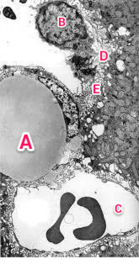

TEM of a part of the liver

A : large fat droplet inside Ito cell B : Kupffer cell C : Blood sinusoid D : Space of Disse E : Microvilli